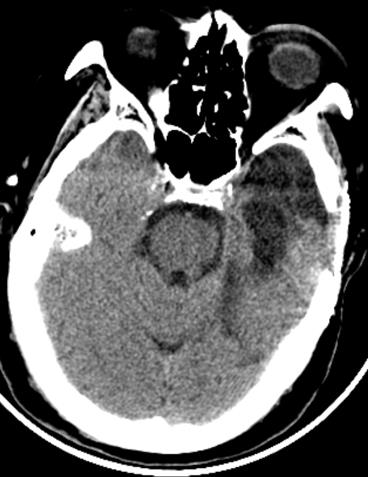

复阅2018年5月9日CT片:右枕顶部软组织肿胀、密度增高,右枕骨见线状骨质断裂、骨折线累及斜坡,右枕部颅板下见梭形致密阴影,大脑镰旁见线状致密阴影,左额颞部颅板下见弧形致密阴影,右额叶及左额颞叶均见斑片状高低混杂密度影,尤以左额叶明显,右侧小脑见斑片状高低混杂密度影。提示右枕顶部头皮血肿,右枕骨骨折,右枕部硬膜外血肿,蛛网膜下腔出血,右颞部硬膜下血肿,右额叶及左侧额颞叶脑挫裂伤,右侧小脑挫裂伤。

图1-5,2018年5月9日 CT片,右枕顶部头皮血肿,右枕骨骨折,右枕部硬膜外血肿,蛛网膜下腔出血,右颞部硬膜下血肿,右额叶及左侧额颞叶脑挫裂伤,右侧小脑挫裂伤